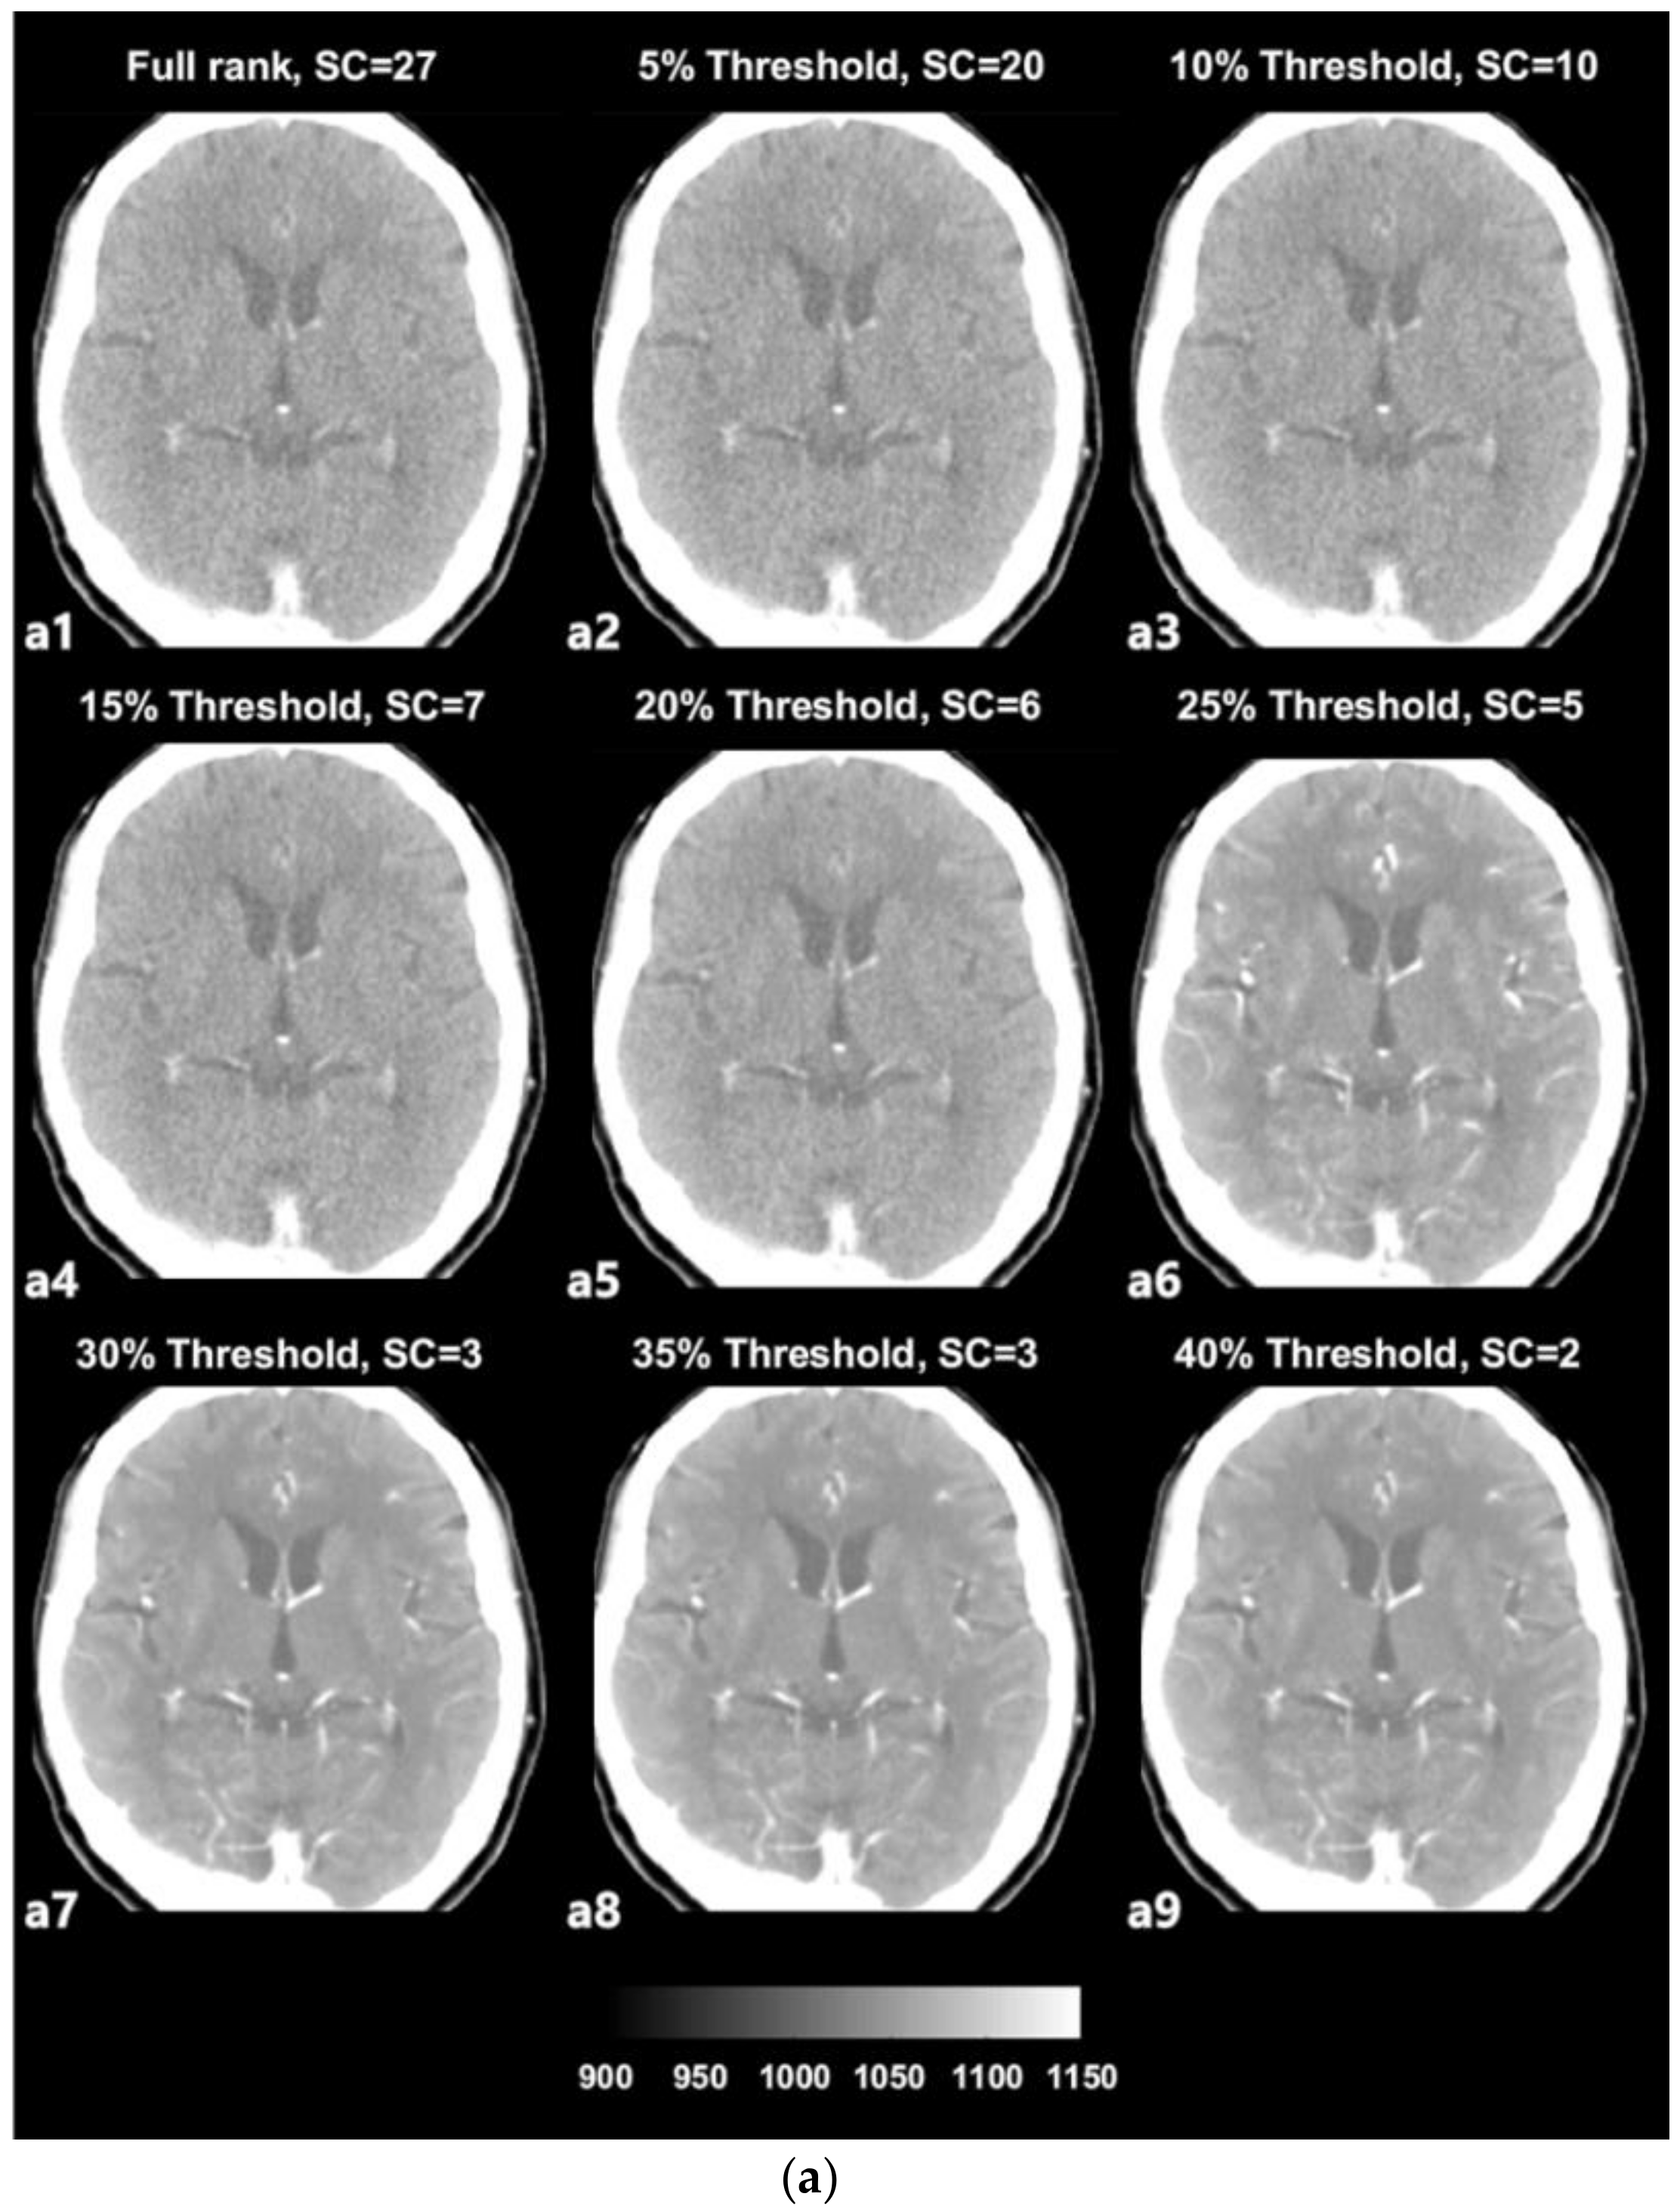

The SVD-based denoising technique was applied to 20 CTP datasets. Each dataset was reconstructed with singular values that were higher than the 5%, 10%, 15%, 20%, 25%, 30%, 35%, and 40% threshold values. Figure 3a depicts an example of denoised images corresponding to increasing thresholds. Figure 3b presents images with noise that were reconstructed with singular values lower than each threshold value and that were separated from the original full-rank image. In an example dataset, a full rank image (original noised Image) includes 27 singular value (Signal Component, SC) components. As shown in Figure 3a,b, the removal of larger amounts of Gaussian noise on an image is observed when the image is reconstructed with a smaller number of SCs (i.e., a larger number of low singular values were excluded).

Figure 3.

(a) Example of denoised images based on thresholding values; a1—original image, a2–a9—denoised images. (b) Example of separated noise components in accordance with thresholding; b1—no noise component was separated from the original image, b2–b9—noise components separated from the original image corresponding to Figure 3.

The term ‘rank’ refers to the number of singular values added to reconstruct a single image [28,29]. The number of singular values in a rank was determined in relation to the threshold value. We selected the 2nd component of the diagonal S matrix as the threshold value on an experiential basis; there is no golden rule to guide the selection of the threshold value because the boundaries of the signal and noise components are still vague and unclear (Figure 2). Thresholding was the process used to approximately classify the singular values in terms of signal components and noise components. The singular values that were lower than the set threshold percentage value (2nd component) were assumed to be singular value noise components in every condition and were subsequently reconstructed into a noise-containing image (Figure 3b). In contrast, the singular values that were higher than the set threshold percentage value (2nd component) were assumed to be singular signal components in every condition and were subsequently reconstructed into a denoised image (Figure 3a).

In the used dataset, the full-rank image (original image, a1) included 27 SCs (Figure 3a), i.e., the 1st to the 27th components, which were in decreasing order of magnitude and were not yet classified. In the case of Figure 3a from a2 to a9, with increasing threshold percentages, larger numbers of components were classified as noise components, resulting in denoised images. For example, in the case of (Figure 3a, a2), the 1st to the 20th singular values were included to reconstruct the denoised image labeled as the 5% threshold image, and the 21st to the 27th singular values that were lower than 5% of the 2nd component were separated from the full-rank image and used to reconstruct the separated noise-containing image (Figure 3b, a9). The image a9 that is labeled as 40% of the threshold image was reconstructed including only the 1st and 2nd singular values by separating the largest number of SCs (25 SCs) from the full-rank image. Nonetheless, the image still appears to exhibit sufficiently high image quality. Regarding image a9, the 1st and 2nd singular values are predominantly depicted as providing diagnostic information. However, it is difficult to confirm that the image at the 40% threshold is the best one, as it simply involves the separation of a larger number of noise-related patterns; reducing the noise on a medical image is inevitably a trade-off for acquiring diagnostic information.